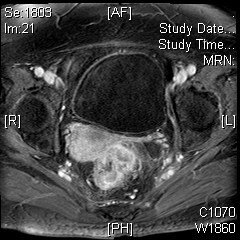

直腸腫瘤入侵鄰近的子宮